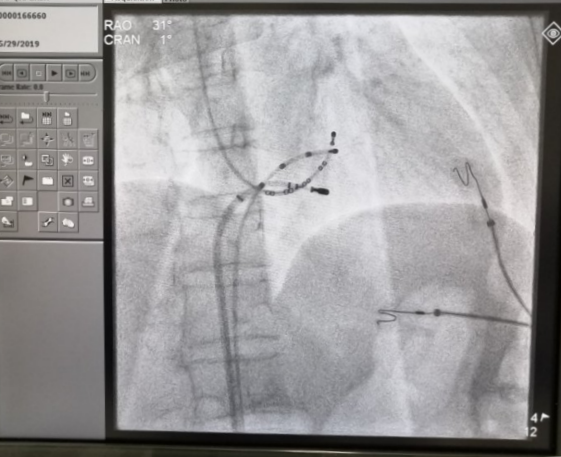

心内电生理检查诊断为房室结双径路所致阵发性室上性心动过速

阵发性室上性心动过速是指起源于心房或房室交界区的心动过速,大多数是由于折返激动所致,少数由自律性增加和触发活动引起。室上速通俗来讲是正常心脏多了一条“电线”、“捷径”或者“中转站”房室结内电流在环路上不停转圈。该病是个终身疾病,导管射频消融可以达到根治。

射频消融靶点处